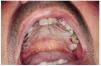

La exploración física mostró en los dos tercios posteriores del paladar duro y parte anterior del paladar blando múltiples pápulas y placas blanquecinas, induradas, no desprendibles con el depresor, que confluían en una gran placa sobreelevada, con la superficie irregular, mamelonada, fisurada, y los bordes bien delimitados, irregulares, con múltiples escotaduras. En algunas placas menos sobreelevadas de la zona más anterior se observa un discreto punteado eritematoso (fig. 1).

FIG. 1.--Gran placa blanquecina localizada en paladar duro.